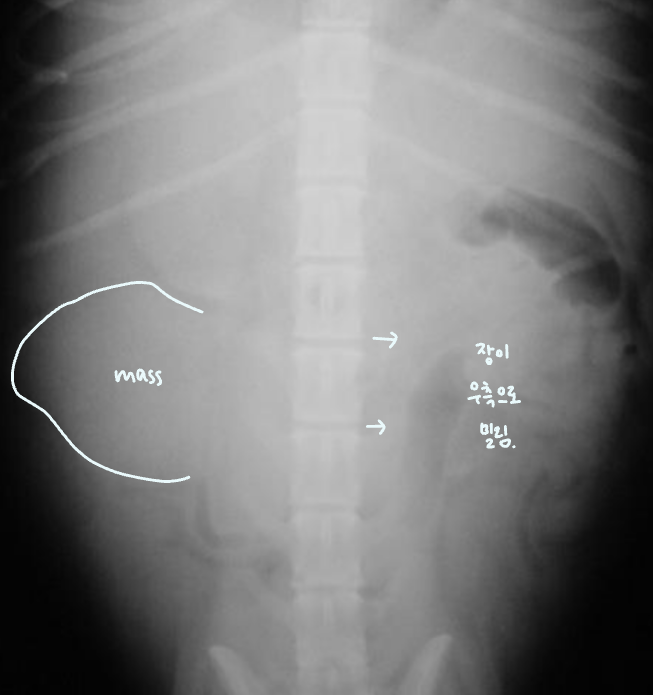

Fluid or Mass

- Fluid : ์ธ์ธก์์์ ์ค์์ผ๋ก ๋ชจ์. diffuseํ ์ฐ๋ถ์กฐ์ง ๋ฐ๋.

- Mass : ์๋ฆฌ๋ฅผ ์ฐจ์งํจ โ ์ฅ์ ๋ฐ์ด๋. & ์ข ์์ด ์ปค์ง๋ฉด์ ์ถํ์ ์ ๋ฐ.